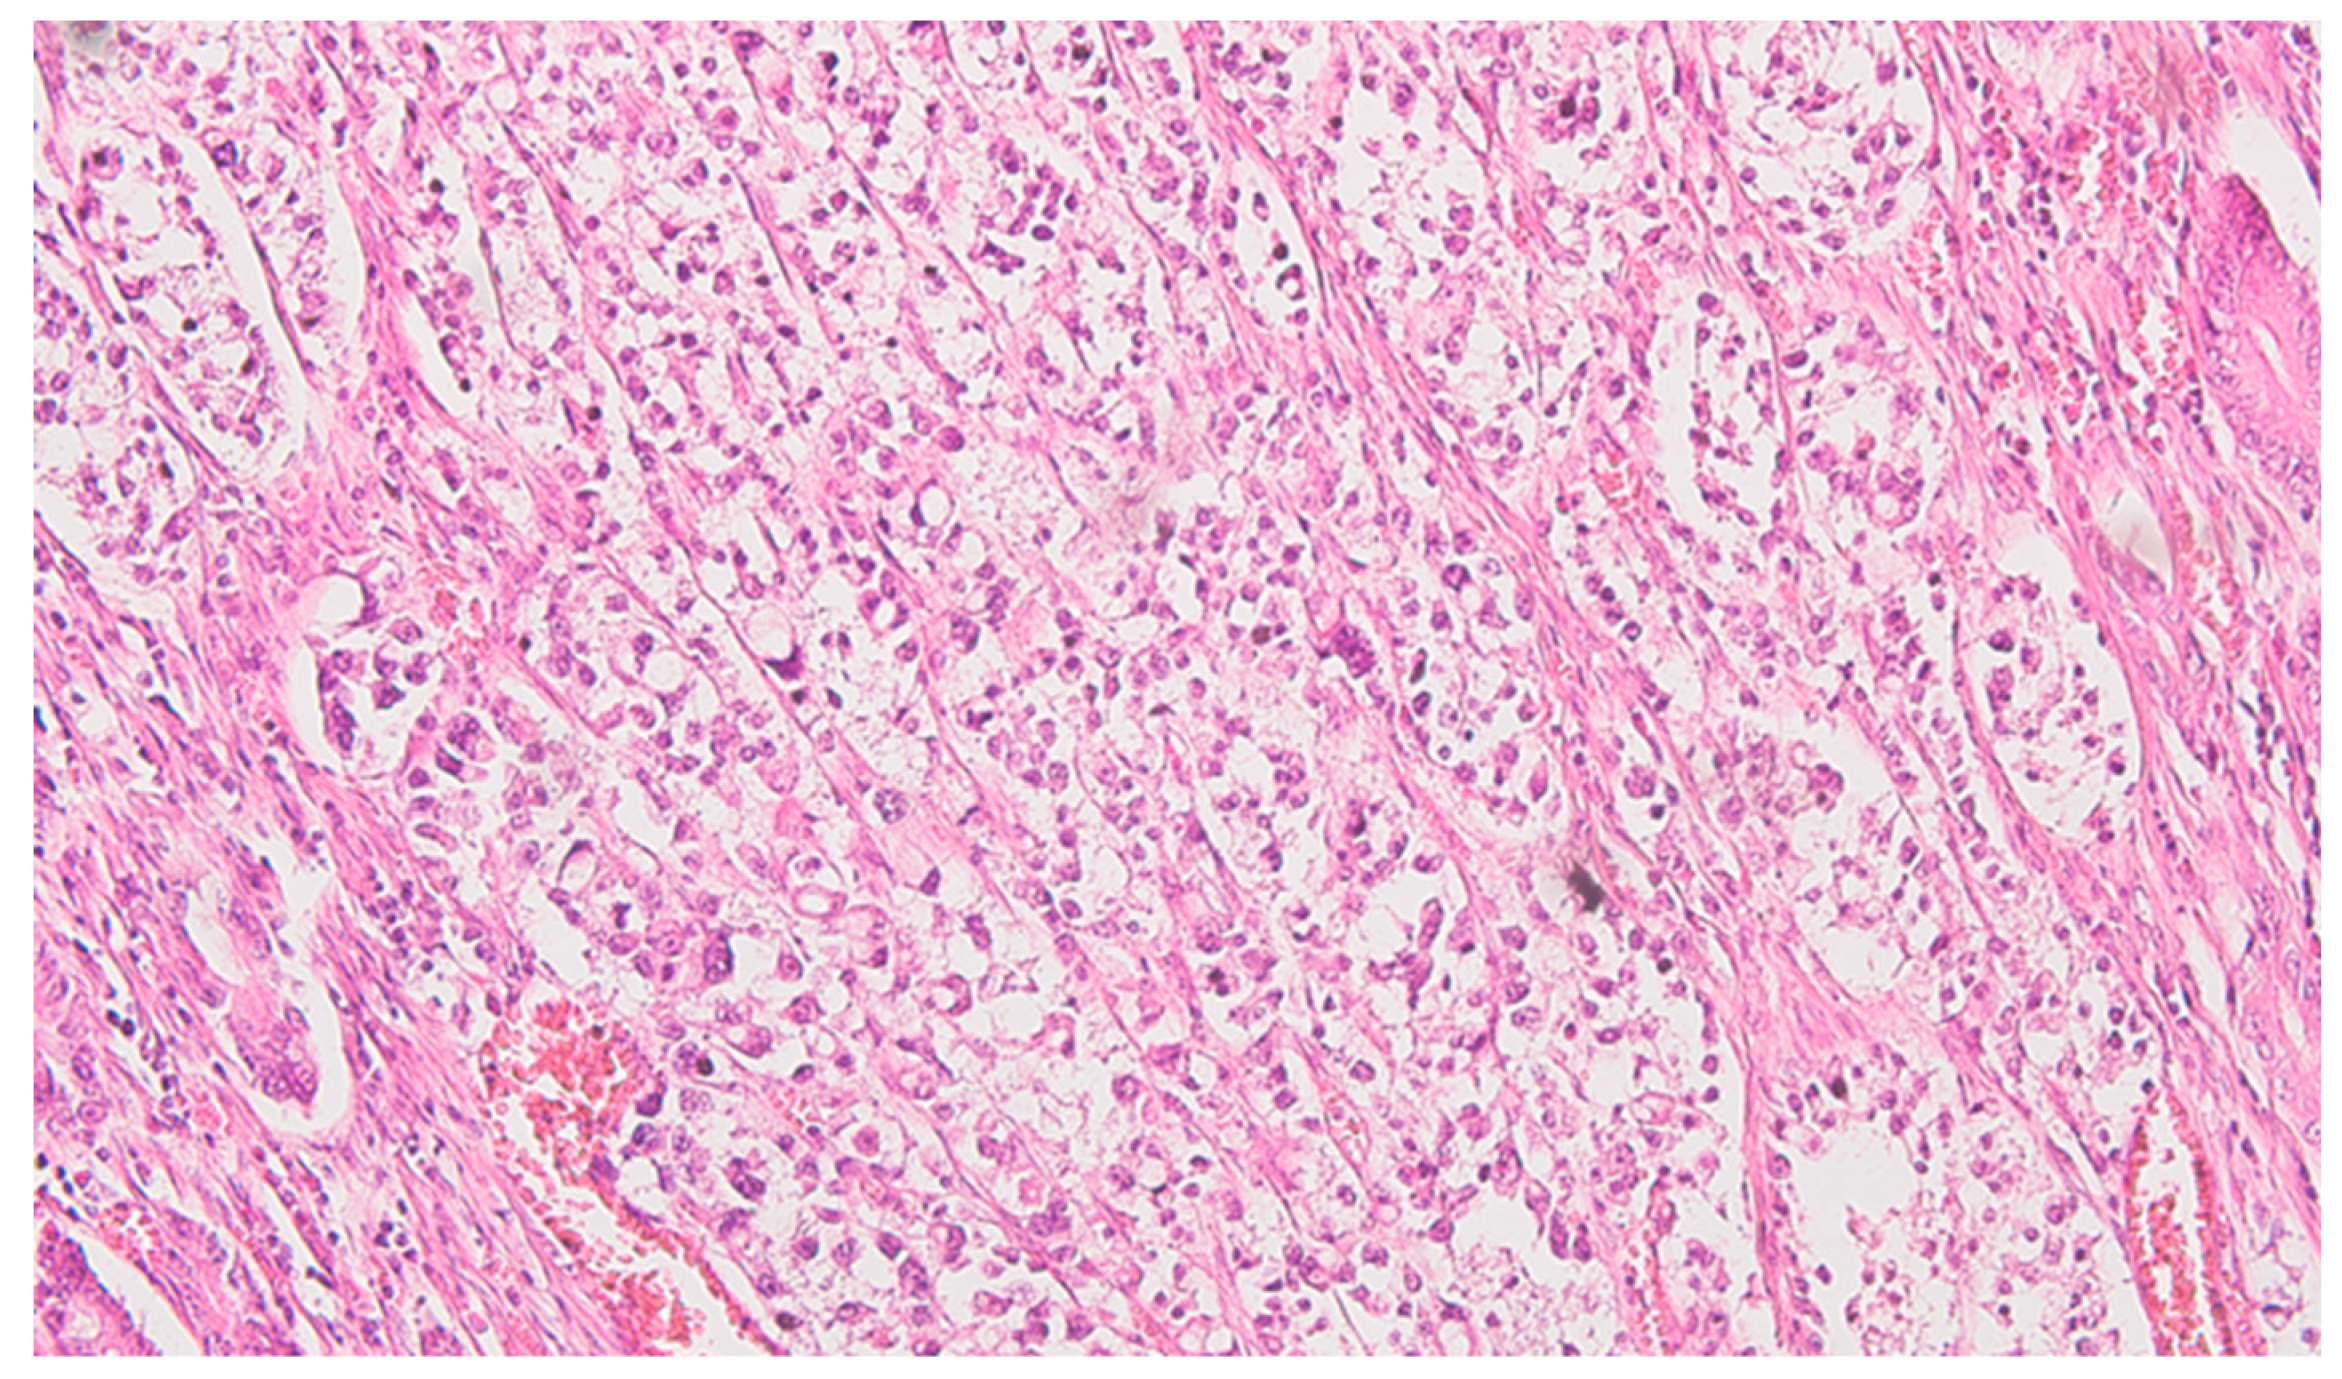

Figure 2. Colon mucinous carcinoma, presence of carcinomatous cells in the subserosa, tangentially to the black ink marking of the peritoneal lining, HE x400.

Serial sections of the ascending colon tumor reveal massive infiltration of a diffuse, mucinous carcinoma, with predominantly intracellular secretion of mucin ("signet ring" cells); some isolated aspects of mucinous tubular adenocarcinoma are also observed. The tumor is ulcerated on the surface, extensively invades the submucosa (Figure 1), and dissociates the muscular layer (muscularis propria), being found massively in the subserosa (Figure 2), with perforation of the visceral peritoneum: tumor cells in ink or less than 1 mm from the inked serosa (pT4a); numerous lymphatic tumor emboli, frequent aspects of perineural invasion. Of 26 lymph nodes, 24 show massive carcinomatous metastases (adenocarcinoma type, Figure 3) - pN2b.